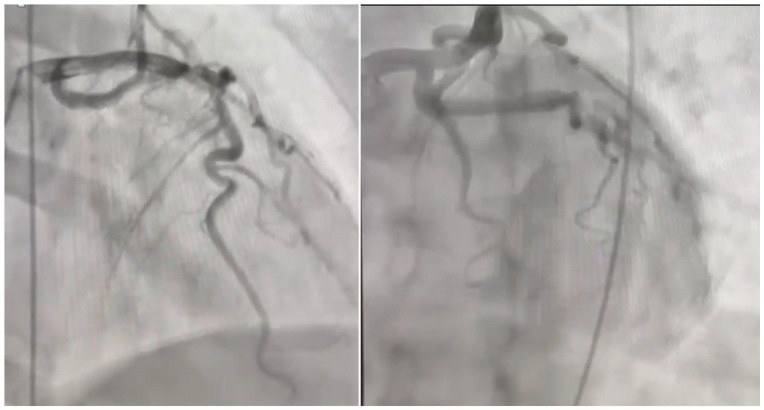

Mid-ventricular Takotsubo cardiomyopathy (TCM) is a variant of Takotsubo syndrome characterized by transient akinesis or dyskinesis of the mid-ventricular segments of the left ventricle, with sparing of the apical and basal segments. This differs from the typical apical form, which involves akinesis of the apical segments and hyperkinesis of the basal segments. Herein, we describe a unique case of mid-ventricular TCM presenting as cardiac asthma in a postmenopausal woman. Our patient reported a 2-day history of shortness of breath and intermittent wheezing that persisted even with respiratory treatment. Triage blood tests showed elevated troponin levels, and electrocardiogram was notable for septal Q waves, raising concern for acute coronary syndrome (ACS). Left heart catheterization revealed nonobstructive coronary artery disease, and ventriculography revealed mid-ventricular dyskinesia with a hypercontractile apex and base, consistent with mid-ventricular TCM. The ACS protocol was aborted, and the patient was managed conservatively with beta-blockers. Repeat echocardiogram at the 3-month follow-up showed recovered heart function, with no wall motion abnormalities.